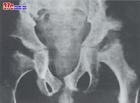

Ⅳ型的臨床特點為明顯的生長遲緩,步態異常和骨骼畸形且逐漸顯著。骨骼的畸形表現和I-S型相似,脊椎的鳥嘴突,椎骨扁平,飄帶肋骨,還可有雞胸,骨質疏鬆,髂骨外翻,股骨頭變平,腕和膝關節腫大,但無關節強直。顏面呈頜骨突出,鼻矮,口大、牙間隙寬及牙釉質發育不良。學齡期出現角膜混濁,皮膚增厚且鬆弛。智力發育基本正常為Ⅳ型的特點。青春期發育可正常。逐漸出現脊髓壓迫症狀,晚期出現麻痹性截癱和呼吸麻痹。病人壽命多為20~30歲。

臨床重型表現多從2~3歲開始生長遲緩,關節活動嚴重受限,頸短,角膜混濁發生較早,顱骨蝶鞍呈鞋型,顱骨縫早閉合可引起神經系症狀,出現腦積水和痙攣性偏癱。骨骼畸形的程度個人間差異較大,逐漸發生骨骼畸形如I-H型上肢長骨受累比下肢重。可有肝脾腫大。智力正常,但可有眼失明和耳聾。心臟亦可有異常可引起死亡,壽命多不超過10歲。

(1)類風濕型粘多糖病:Winchester等於1969年發現兩例同胞病兒,他們的臨床表現與粘多糖病I(H)型相似,而骨骼變化似類風濕性關節炎,X線照片表現為進行性溶骨性破壞,尿中排出的粘多糖量正常。通過皮膚纖維母細胞組織培養證實為粘脂質代謝障礙。